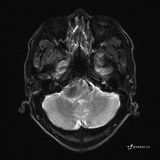

患者男,51岁。

简要病史:患者自述于1周前至某人民医院发现脑干肿瘤(具体不详),为求进一步诊断至我院就诊。

完善颅脑MRI平扫+增强,颅脑CT平扫:

T2: